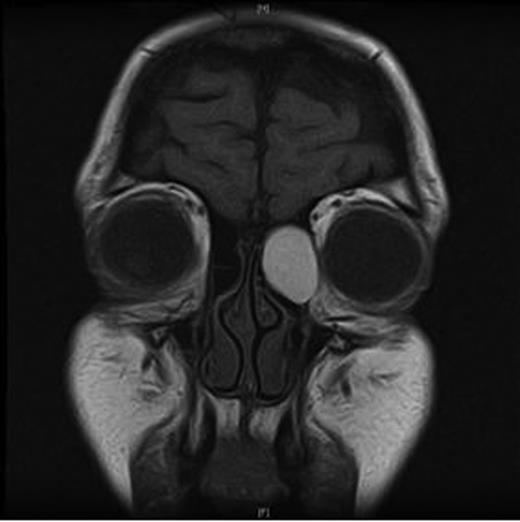

An MRI scan of the orbits showed a well-defined, thin-walled 22 × 16 mm cyst medial to the left orbit containing fatty/proteinaceous material, which was lying within and mildly expanding the left ethmoid air cells (Figs 1–3).